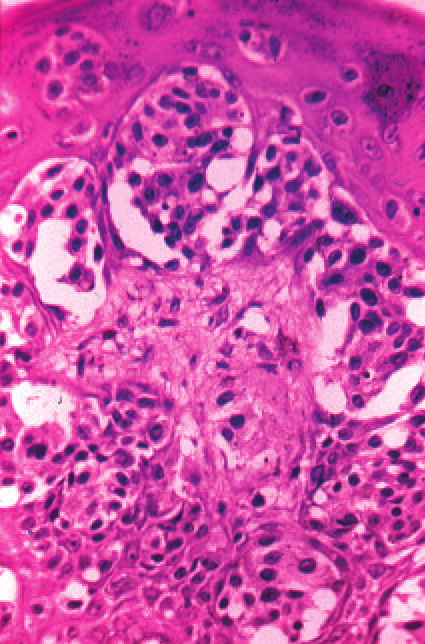

Histopathology.

Architectural pattern features of importance in the diagnosis include the large diameter of the lesions, poor circumscription (the last cells at the edge of the lesion tending to be small, single, and scattered), and asymmetry (one half of the lesion does not mirror the other half) . The epidermis is irregularly thickened and thinned, in contrast to the uniformly elongated rete ridge pattern of a dysplastic nevus . Rather uniformly rounded, large melanocytes are scattered in a pagetoid pattern throughout the epidermis. The large cells lie predominantly in nests in the lower epidermis and singly in the upper epidermis. The nests tend to vary a good deal in size and shape and to become confluent. Dermal melanophages and a dermal infiltrate are regularly present. The lymphocytic infiltrate may be patchy and perivascular as in a dysplastic nevus but is typically dense and bandlike, especially in invasive lesions.

Cytologically, the lesional cells are rather uniform and have abundant cytoplasm containing varying amounts of melanin that often consists of small, "dusty" granules. They are almost entirely devoid of readily visible dendrites. The nuclei tend to be large and hyperchromatic, with irregular nuclear membranes and irregularly clumped chromatin . This uniform cytologic atypia is of considerable diagnostic importance and contrasts with the random cytologic atypia of dysplastic nevi.

When the lesion is in situ, the basement membrane is intact  and there are no lesional cells in the dermis. In an invasive but nontumorigenic lesion (invasive radial growth phase or microinvasive melanoma), cells similar to those in the epidermis are present in the dermis in the form of small nests, with no nests larger than those in the epidermis, and with no dermal mitoses . When tumorigenic vertical growth phase is present, there is at least one, or often more than one, cluster of cells in the dermis that is larger than the largest intraepidermal nest, and/or there may be lesional cell mitoses in the dermis .